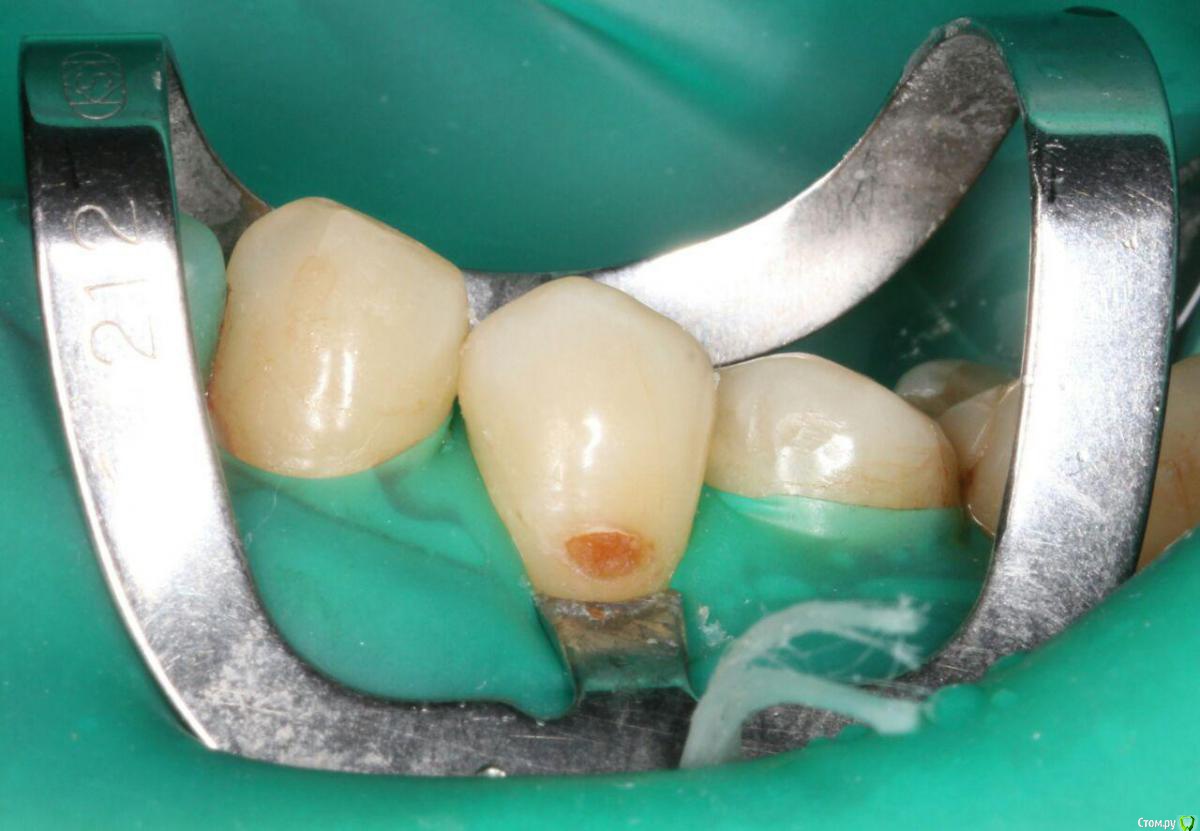

Бардо Опубликовано 1 июня, 2017 Поделиться Опубликовано 1 июня, 2017 (изменено) Так-то я свои белые линии вроде поборол, кроме таких вот бесячих пришеек. Часто по нижнему краю образуется, сволочь. . Здесь линии вроде нет, но проблема есть. Куда копать, кто подскажет? Полирую эмалевый скос перед бломбой красным бором и торовскими синими дисками обычно. Синглбонд2 без спирта. Другой бонд мне не дают Изменено 1 июня, 2017 пользователем Бардо 1 Ссылка на комментарий